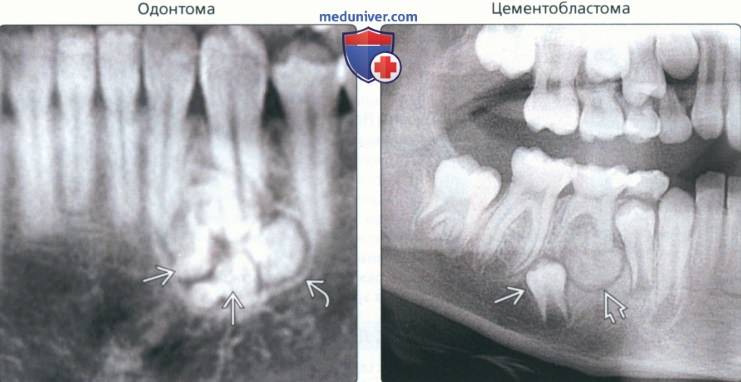

Одонтома нижней челюсти: фотографии и медицинская информация